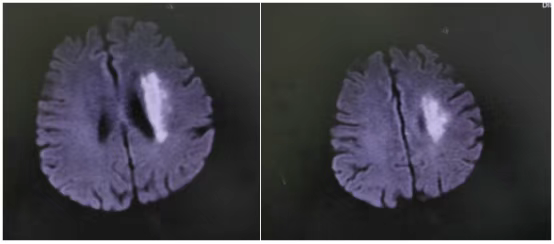

那天,71岁的符阿婆在家突发右侧肢体无力,说话也变得含糊不清。紧急送医后,检查结果令人揪心——左侧大脑中动脉M1段闭塞。

“当时情况非常紧急,”主管医生刘婷回忆道,“造影后发现符阿婆血管闭塞远端血流灌注严重不足,考虑是‘低灌注’导致核心梗死区周围的脑组织(缺血半暗带)也濒临坏死边缘。这意味着,虽然发病时间已较长,但仍有大量脑组织处在‘生死边缘’,若不立即干预,瘫痪将不可逆转。”

“时间就是大脑,虽然超过了常规时间窗,但根据最新的诊疗理念和影像学评估,我们判断患者仍存在可挽救的脑组织。”李威副主任医师解释道,“大脑中动脉全程闭塞,就像一棵树的主干被砍断,远端所有枝叶都将枯萎。我们必须尽快‘接通’主干,恢复血流。”

手术台上,一场与时间的赛跑再次开启。介入团队在DSA(数字减影血管造影)的精确引导下,将微导管、球囊等器械精准送达大脑深处闭塞的血管处。首先用球囊扩张,撑开狭窄闭塞的血管,随后成功植入一枚支架,牢牢“撑住”了病变血管,重建了血流。

术后,符阿婆右侧肢体的肌力很快开始恢复。经过后续系统的药物治疗和康复训练,她右侧肢体力量显著改善,言语功能也逐步清晰,恢复良好,最终顺利出院。